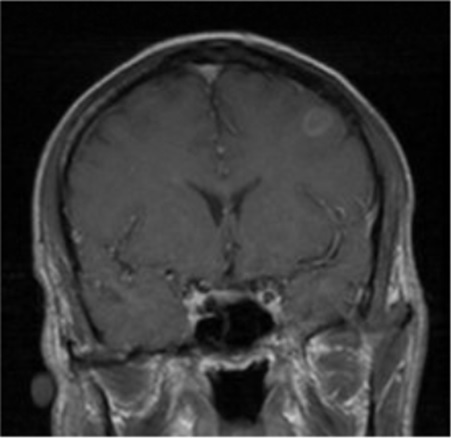

Case Presentation: A 36 year old male from Central America who immigrated to the United States ten years ago presented with cough and headache accompanied with fevers. He did not have any past medical conditions. On admission his vitals were T 39.1 C, HR 114, RR 20, BP 129/85 mmHg. He was noted to have oral thrush and his lungs were clear to auscultation. No neurological deficits were appreciated. Due to the oral thrush he was tested for HIV. His HIV-1 antibodies resulted positive, his absolute CD4 T-cell count was 61 cells/uL and HIV viral load was 36,500 copies/mL. A chest CT revealed nodular infiltrates in the right lower lobe with one of the infiltrates demonstrating a 0.7 cm central cavity. His serum cryptococcal antigen was positive and his blood cultures grew cryptococcus. His TB interferon gamma release assay was negative. He was initiated on amphotericin and flucytosine for disseminated cryptococcal infection with pulmonary involvement. Meanwhile, his lumbar puncture showed 4 total nucleated cells/uL with 25% neutrophils, 65% lymphocytes, CSF glucose was 62 mg/dL and protein was 35 mg/dL, cryptococcal antigen and toxoplasmosis IgG were positive and toxoplasma IgM and AFB smear were negative. Brain MRI with contrast showed a peripherally enhancing 1 cm lesion in the left middle frontal gyrus with mild surrounding vasogenic edema and minimal mass effect.On the discovery of the above ring enhancing lesion there was concern that the patient might have a disseminated cryptococcal infection as well as a concurrent toxoplasma CNS infection, albeit with a singular lesion instead of the commonly seen multiple lesions. Pyrimethamine, sulfadiazine and leucovorin were administered empirically and CSF EBV and toxoplasma PCR testing was sent. However, symptomatically, prior to the initiation of toxoplasma treatment, the patient’s headache had started to resolve and since the lesion was not typical of a toxoplasma CNS infection, further treatment for same was held until confirmatory tests resulted. Eventually, CSF toxoplasma PCR and EBV PCR testing resulted negative and the patient was continued on anti-fungal treatment for disseminated cryptococcal infection with a possible cryptococcoma. In time, CSF cultures demonstrated growth of cryptococcus as well.

Repeat brain MRI with contrast (2 weeks after initiation on antifungal treatment) showed an interval decrease in the size of the previous noted lesion along with a decrease in surrounding vasogenic edema.

Conclusions: The patient’s subsequent lumbar punctures during his hospitalization did not show growth of the fungus. Repeat brain MRI prior to discharge showed a minimal decrease in the size of the lesion and complete resolution of surrounding vasogenic edema. He was discharged home with appropriate treatment to follow-up with Infectious Disease specialists as an out-patient.